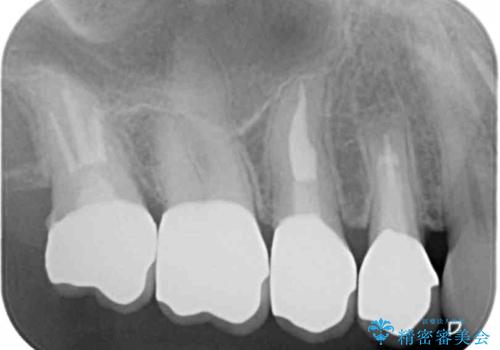

臼歯部メタルフリー再補綴

- 110万円(仮歯×8・ファイバーコア×6・ジルコニアクラウン×8)費用は治療当時の料金となります

装着して長期間経過したブリッジやクラウンは隙間から細菌が侵入し虫歯が再発してしまっていることがあります。

長期的に問題のないブリッジ・クラウンを作製するため、虫歯をしっかりと除去すること精密な根管治療を行うことが肝要です。